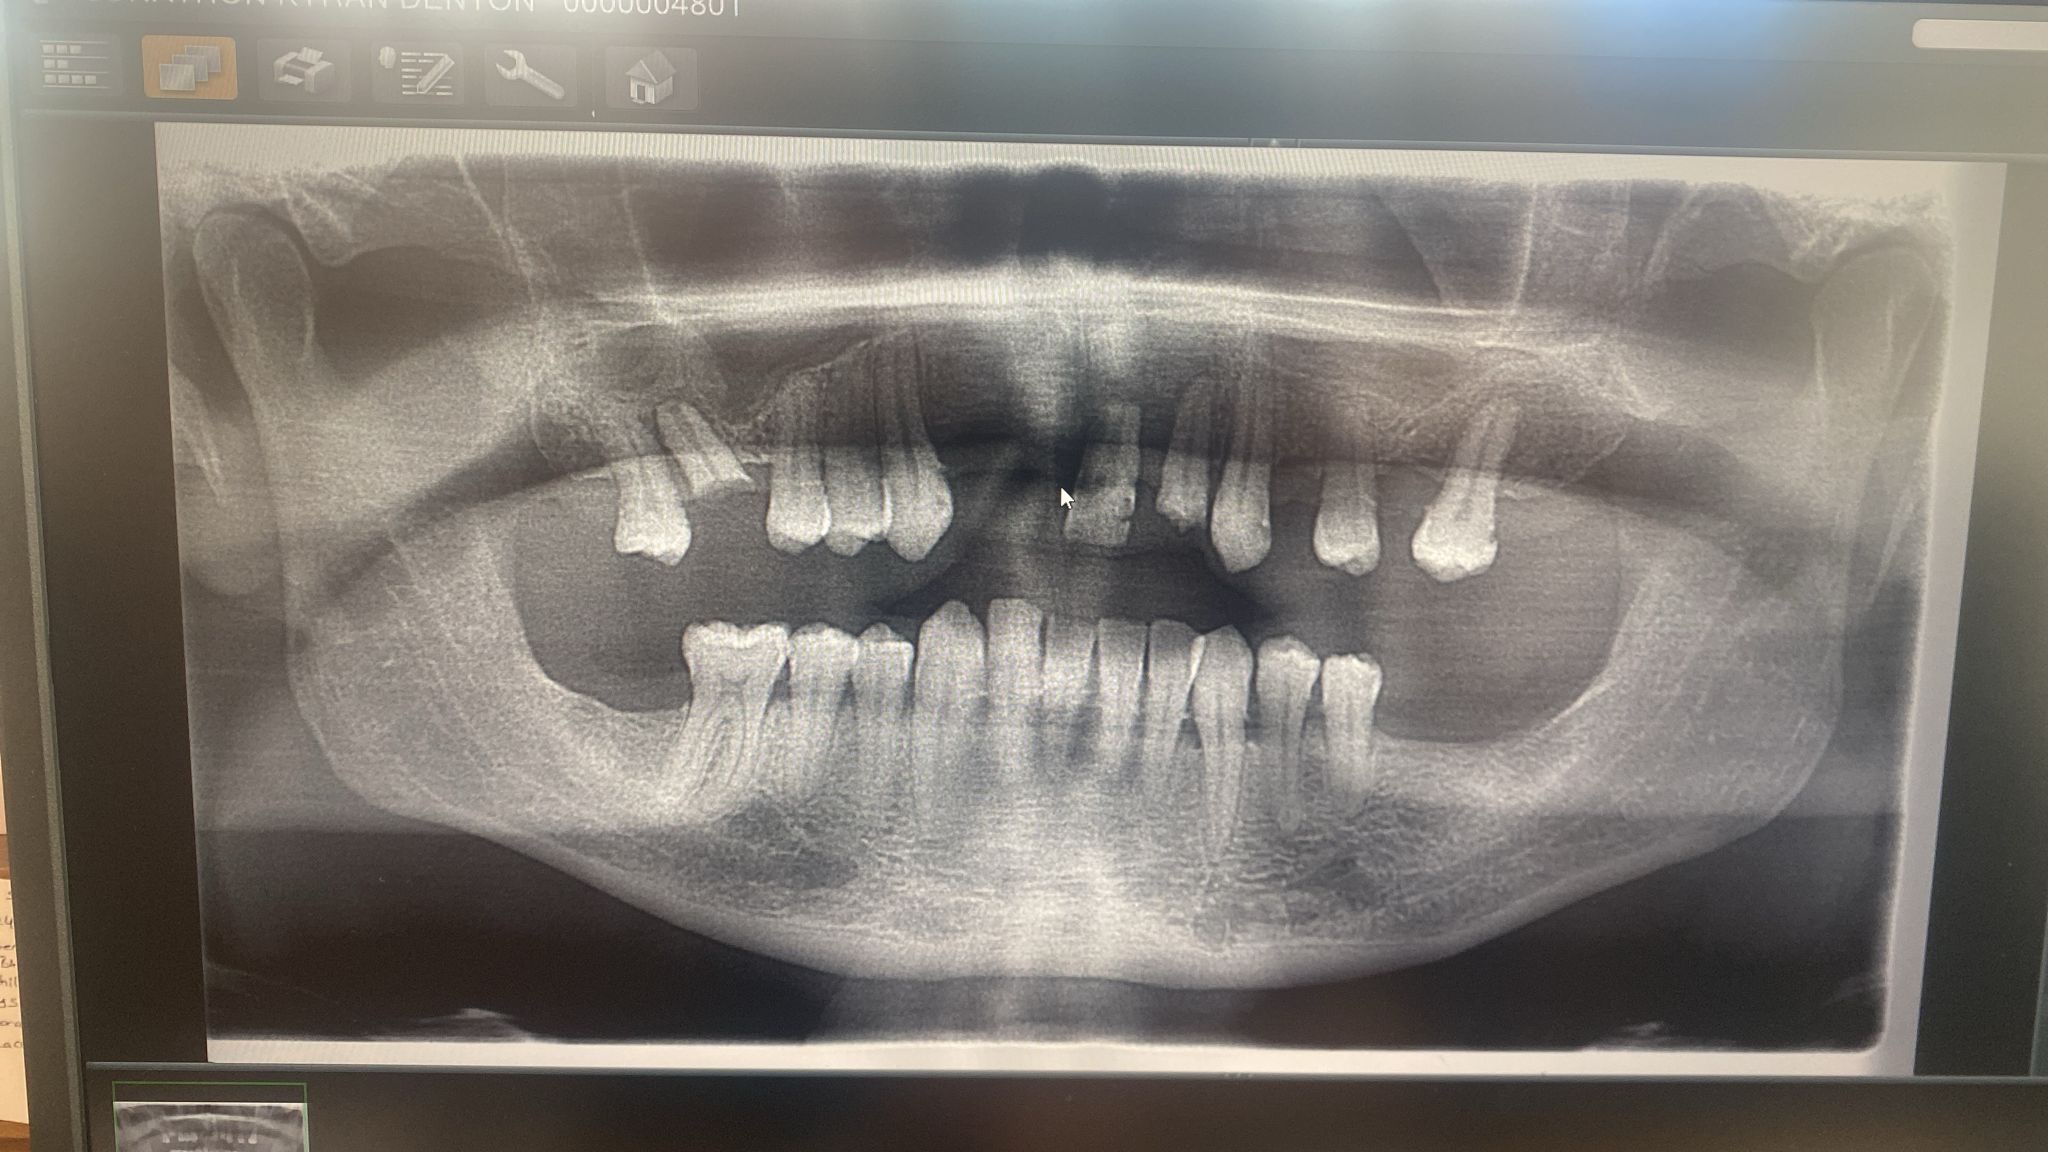

Six years ago, Jon was involved in a serious bike accident. During emergency treatment, paramedics had to remove his front tooth to get a tube down his throat. The accident caused significant trauma to his teeth, and over time they deteriorated and began to crumble, making it increasingly painful for him to eat.

When Jon returned to the UK, he immediately saw his GP, who confirmed that he does NOT have diabetes. He also visited a dentist, who diagnosed a severe gum infection. He was told that the antibiotics previously prescribed were ineffective and was given a new course to properly treat the infection.

The clinic had prescribed those same ineffective antibiotics both at the start of treatment and again when his implants were removed. From what Jon has since been told, if an infection had been present from the beginning, it could have contributed to the implants failing, but this was not properly identified or managed.

Since having a 3D scan in the UK we have determined that the treatment abroad should never have gone ahead as Jon did not have sufficient bone to support the implants, this along with an infection they failed to treat. What bone he did have was damaged by implanting and removing implants. Sinus lift was also not carried out as told and very minimal if any signs of a bone graft were found on 3D scan. Jon had no ridge so dentures are not suitable for him and they just fall out, despite trying all adhesives recommended.